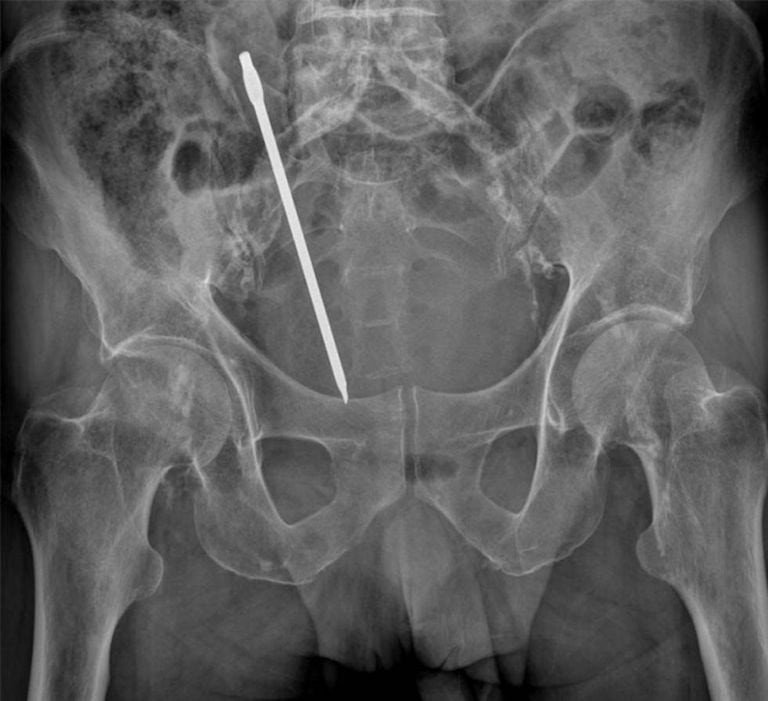

Num dia de 2015, um homem de 50 anos chegou ao pronto-socorro do Hospital Universitário de Getafe, na Grande Madri. Relatava prisão de ventre. Na radiografia não havia nada de estranho, então os médicos lhe administraram um enema de limpeza. Ao cabo de algumas horas em observação, o homem não suportava a dor abdominal. “Tinha taquicardia e suores”, recorda uma das médicas que o atenderam, Myriam Valdés. Uma tomografia revelou então “um objeto estranho no cólon” e uma peritonite fecaloide decorrente de uma perfuração do intestino. Na sala de cirurgia, os cirurgiões encontraram uma cenoura de 20 centímetros inserida por via anal.

Um hospital da Espanha atendeu um homem de 50 anos com uma cenoura de 20 centímetros no reto